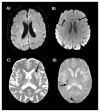

Figures